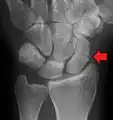

Radiolucency around a 12 days old scaphoid fracture that was initially barely visible.[13]

Scaphoid fractures are often diagnosed using plain radiographs and multiple views are obtained as standard.[9] However, not all fractures are apparent initially.[7] In 1/4 of cases, the clinical examination suggests a fracture, but the X-ray does not show it, even though there is indeed a fracture.[10] Therefore, people with tenderness over the scaphoid (those who exhibit pain to pressure in the anatomic snuff box ) are often splinted in a thumb spica for 7–10 days at which point a second set of X-rays is taken.[7] If a minimally displaced fracture was present initially, healing will now be apparent. Even then a fracture may not be apparent. A CT Scan can then be used to evaluate the scaphoid with greater resolution. The use of MRI, if available, is preferred over CT and can give one an immediate diagnosis.[11] Bone scintigraphy is also an effective method for diagnosis fracture which do not appear on Xray.[12]